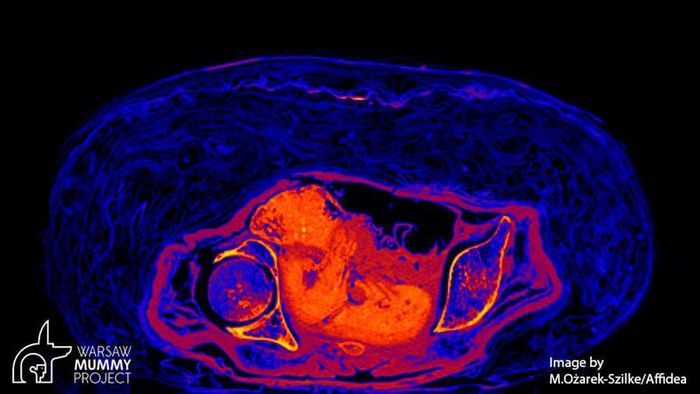

Kết quả cho thấy xác ướp không phải là của linh mục Hor-Djehuty. Thay vào đó, thi hài thuộc về một phụ nữ tử vong khi mang thai. Thai nhi đang ở tuần thai thứ 26 - 30.

Sau khi tử vong, thai phụ trên được ướp xác cùng với bào thai trong bụng. Từ đây, các chuyên gia đặt ra hàng loạt câu hỏi như: người phụ nữ này là ai? Tại sao bà được ướp xác cùng với thai nhi?...

Trước sự việc này, nhà khảo cổ học Wojciech Ejsmond thuộc Học viện Khoa học Ba Lan cho biết bào thai đã không được lấy ra khỏi bụng mẹ như trong quá trình ướp xác thông thường.

Chính vì vậy, tính đến thời điểm hiện nay, đây là xác ướp duy nhất được ướp xác với thai nhi nguyên vẹn trong bụng mẹ.

Các nhà nghiên cứu tin rằng việc phân tích các mô mềm được bảo quản của xác ướp có thể mang lại một số manh mối giúp tìm ra nguyên nhân tử vong của thai phụ.

Dù vậy, một số chuyên gia đưa ra giả thuyết người phụ nữ có thể đã gặp một số vấn đề về sức khỏe trong quá trình mang thai. Điều này khiến bà tử vong trong thời gian thai kỳ.